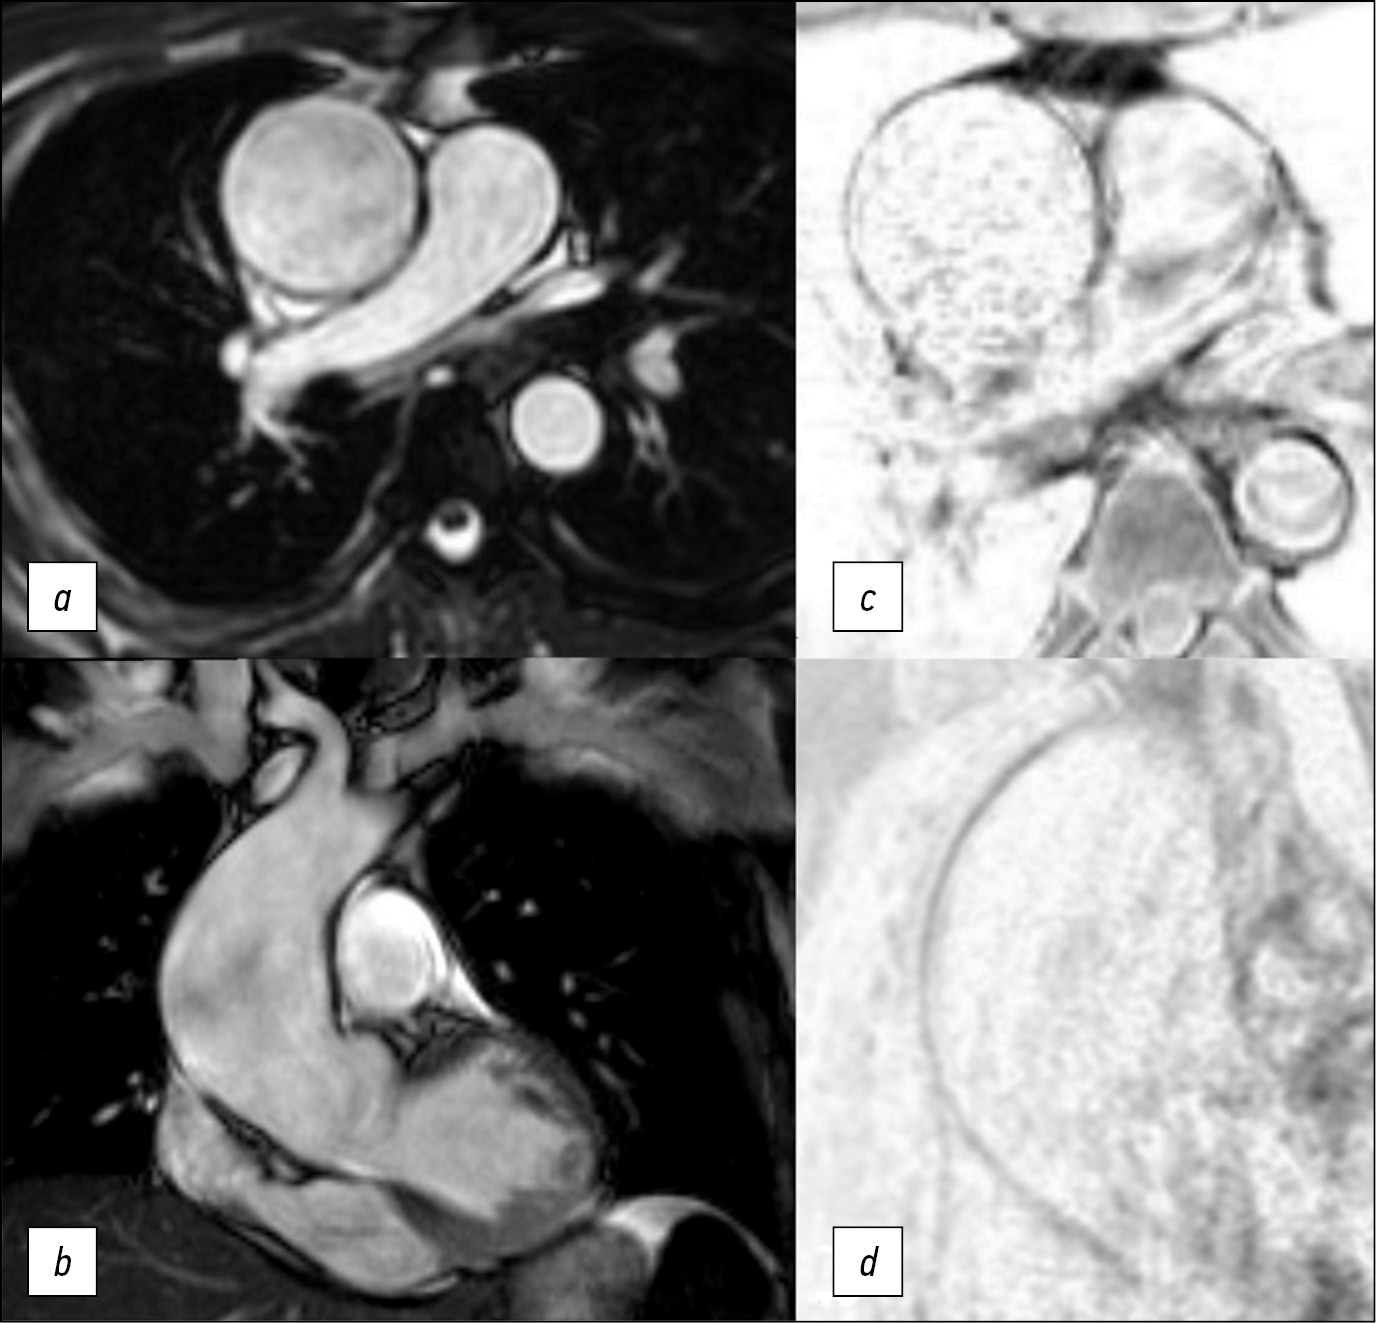

为了评估主动脉壁的弹性和收缩性,使用了在轴向和冠状投影中以稳态自由进动(steady-state free precession, SSFP)模式获得的原生图像(见图1)。

图1。在轴位(a)和冠位(b)中以SSFP模式获得的图像,在轴位(c)中以T1-SE(主动脉瘤的中间三分之一) ,在斜投影中以“黑血”模式获得的T1-SPIR(d)。主动脉壁变薄,中部更明显。

在SSFP模式下,我们能够清楚地显示出心动周期期间主动脉壁的运动和血流方向。在QFlow序列(包括导管的可视化)中进行MRI以定量估值脉搏波速度,或如需评估瓣膜的功能。升主动脉壁的厚度和血管化是通过轴位的T1加权自旋回波(T1-spin echo, T1-SE)和梯度回波(T1-gradient-echo, GRE)序列中取得照片评估的,具有光谱选择性信号抑制的T1加权序列,在“黑血”模式(图2)中的光谱饱和和反转恢复序列(Т1-spectral presaturation with inversion recovery, T1-SPIR),在T2-在轴向和倾斜投影的“黑血”模式中具有光谱抑制的加权序列。